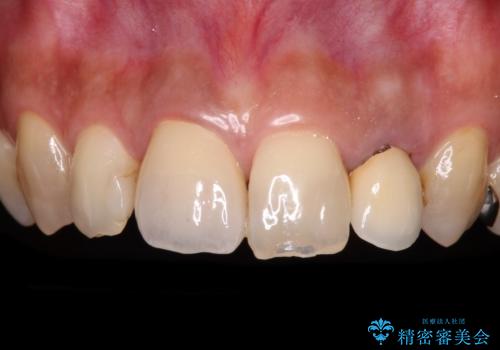

- 矯正治療後に、下顎奥歯の銀歯をすべてゴールドにすることを希望された患者様です。

セラミッククラウンやセラミックインレーによる補綴治療も提案しましたが、お友達にゴールドを自慢したいとのことで、ゴールドクラウンとゴールドインレーにて処置することとしました。